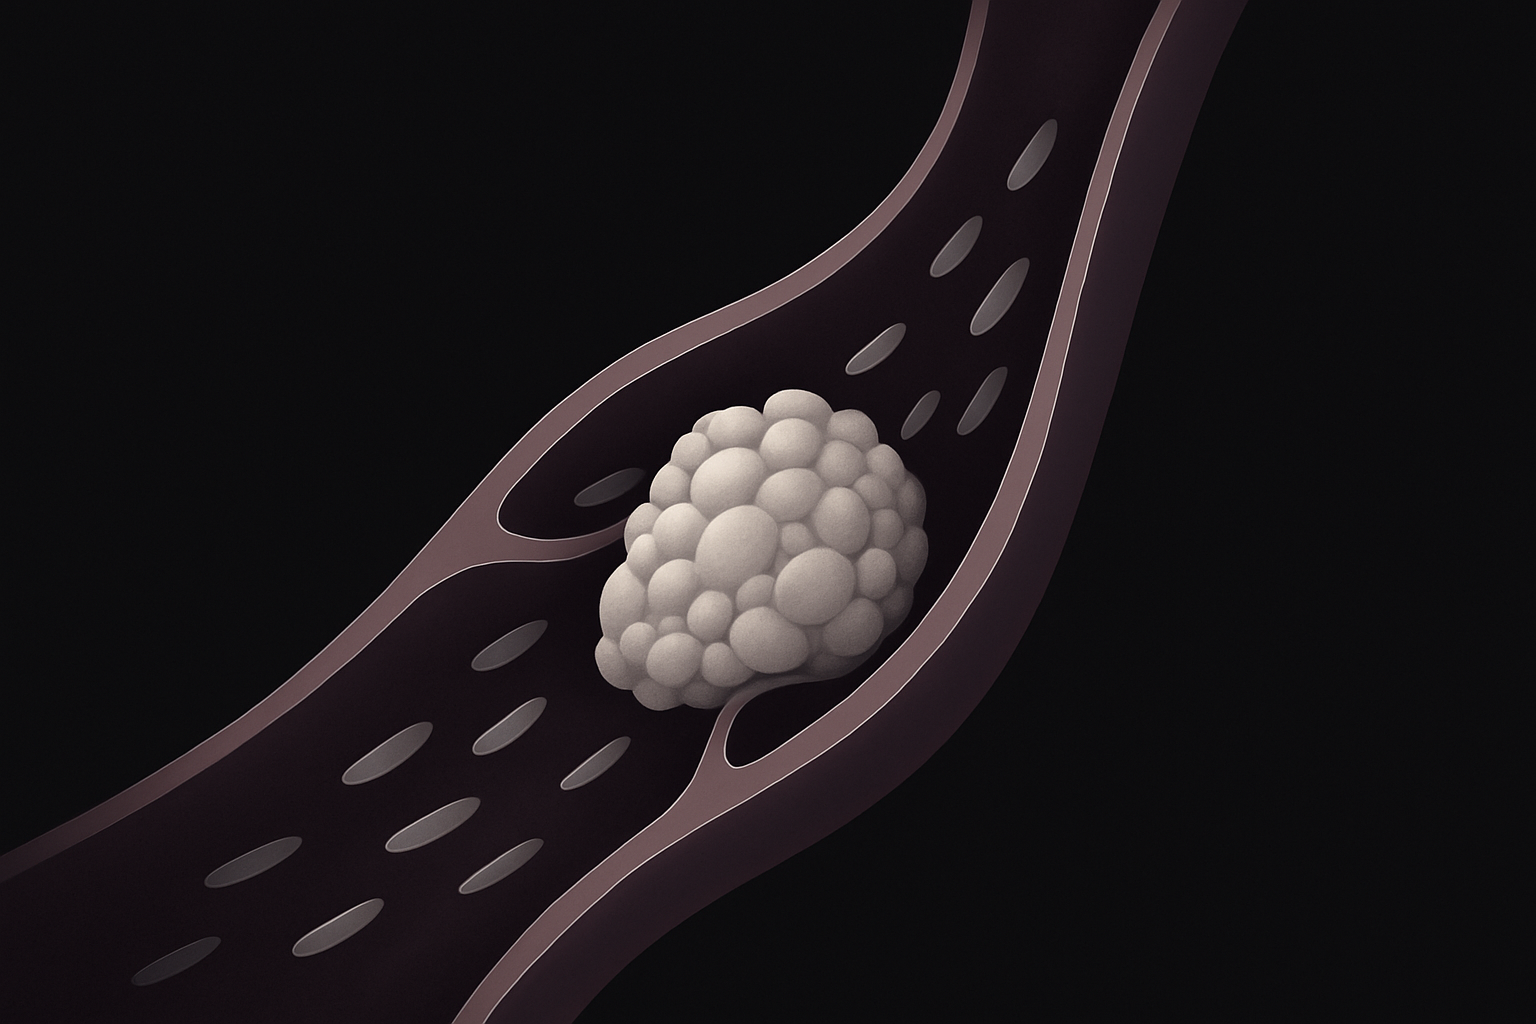

As artérias carótidas ficam no pescoço e levam sangue ao cérebro. Quando essas artérias sofrem um estreitamento (estenose), geralmente por acúmulo de placas de gordura (aterosclerose), há risco de reduzir o fluxo sanguíneo ou até soltar fragmentos da placa, que podem entupir vasos cerebrais e causar derrame (AVC).

- Antiagregantes plaquetários (como aspirina ou clopidogrel) para evitar formação de coágulos.

- Estatinas para controlar o colesterol.